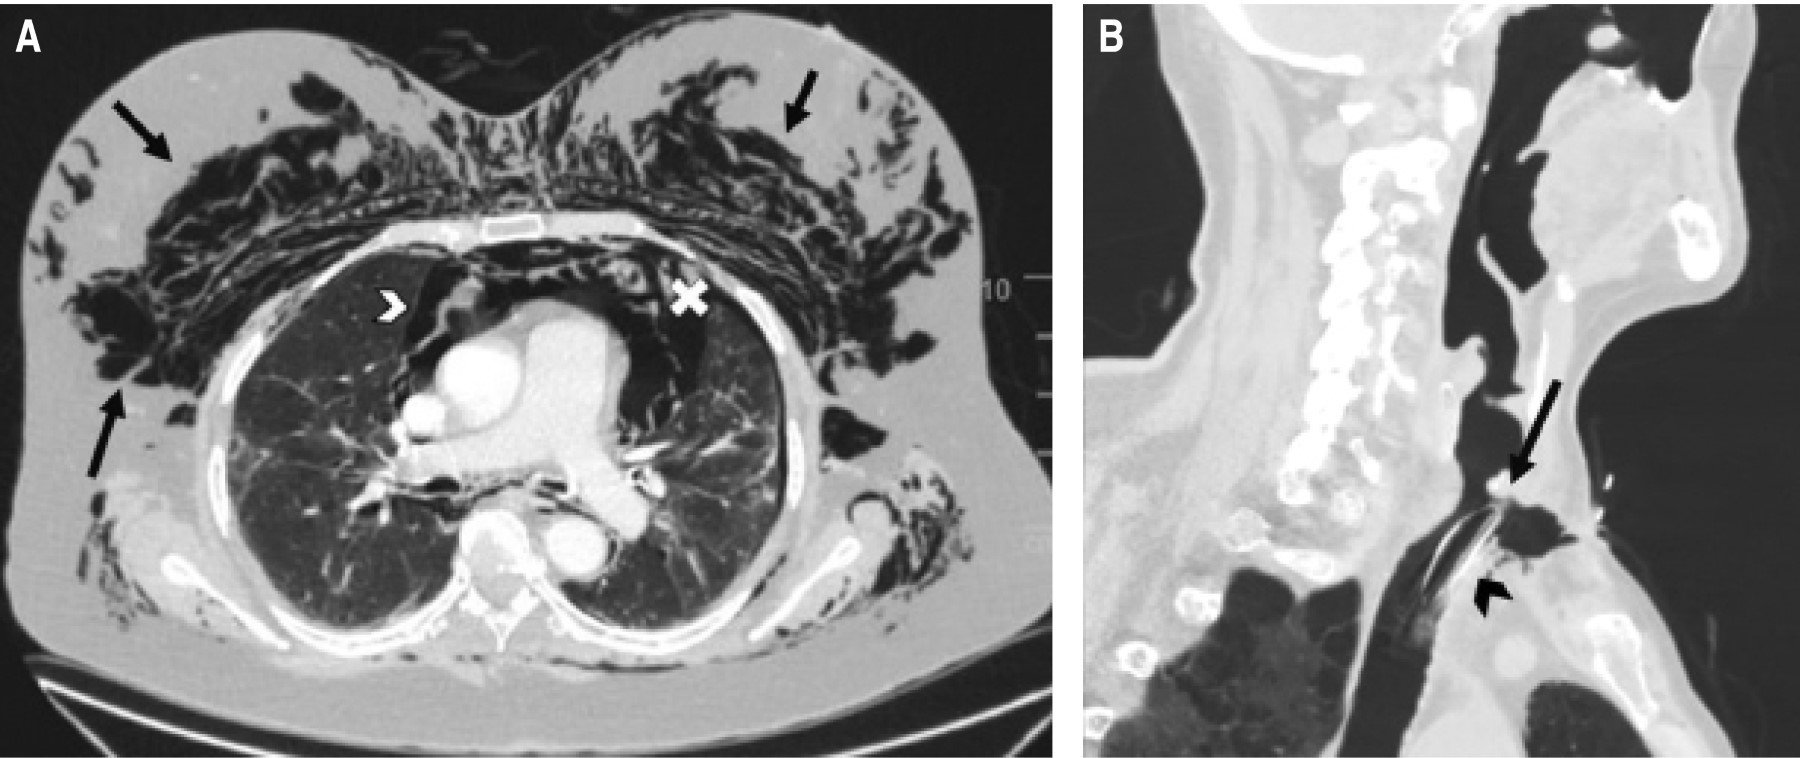

A las 72 horas de la intervención se observó un abundante enfisema subcutáneo cervicofacial. Se llevó a cabo una tomografía computarizada (TC) que describía el enfisema subcutáneo, neumomediastino con compresión traqueal, así como un pequeño neumotórax izquierdo (Figura 1A). A pesar de que en la TC no se evidenciaba una rotura traqueal, se hizo una fibrobroncoscopía que mostró una solución de continuidad de 2 centímetros en la pars membranosa, a nivel de la carina. Ante la estabilidad clínica de la paciente, la ausencia de progresión del enfisema subcutáneo y al tener en cuenta los antecedentes recientes, se decidió llevar a cabo un manejo conservador administrando piperacilina-tazobactam, con lo cual hubo una franca mejoría en los tres días posteriores, lo que permitió el alta a la planta de hospitalización.

El segundo caso fue un varón de 67 años con antecedentes de diabetes mellitus tipo 2 y enfermedad pulmonar obstructiva crónica tipo enfisema. Desarrolló un síndrome de distrés respiratorio agudo causado por el virus SARS-CoV-2, que requirió ventilación mecánica invasiva prolongada y presentó una estenosis traqueal secundaria. Bajo anestesia general, se realizó una broncoscopía rígida para la corrección de la estenosis mediante láser, pero durante el procedimiento se produjo una lesión en la pared traqueal con un flap que obstruía la luz de la tráquea, lo que impidió la correcta ventilación. Se hizo una traqueotomía emergente, en la que se vio la rotura de los dos primeros anillos traqueales, se introdujo una cánula de traqueostomía del número 8 y se trasladó sedorrelajado a la Unidad de Cuidados Críticos Quirúrgicos. Además, se efectuó una TC (Figura 1B) en la que se observó enfisema subcutáneo anterior, un pequeño neumomediastino y un neumotórax izquierdo que necesitó la colocación de un tubo de tórax.

Figura 1